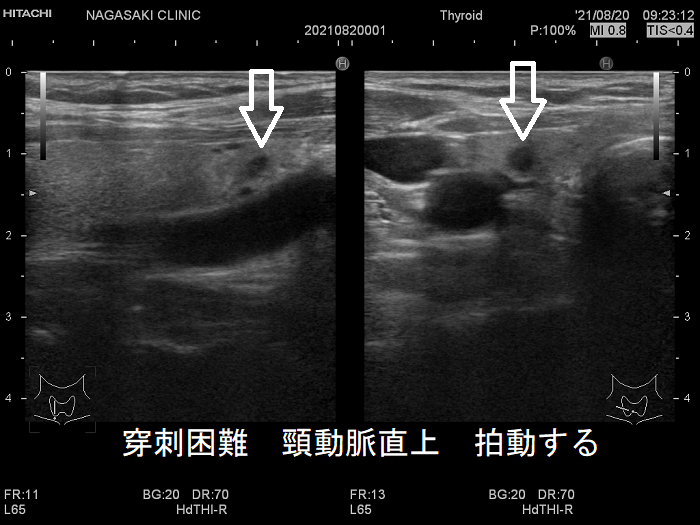

甲状腺穿刺細胞診の主な有害事象の一つは穿刺時出血、穿刺後出血;最悪、気道閉塞により窒息。注意しても唾を飲む方におこる。用手圧迫、再度、超音波エコー、造影CT、喉頭ファイバー行い出血・喉頭腫大を確認後入院。甲状腺機能亢進症/バセドウ病、TSH高値の重度甲状腺機能低下症は甲状腺内部血流が異常増加し穿刺で大出血の危険。甲状腺ホルモン正常化し血流低下を待つ。頚動脈に接する・連鎖して拍動する、下甲状腺動脈直下の小さな甲状腺腫瘍は穿刺難。甲状腺血管腫は何度穿刺細胞診しても血液成分のみで穿刺後出血の危険。最下甲状腺動脈穿刺で大出血。

穿刺細胞診するには、あまりにリスクが大きく、断念せざる得ない場合があります。たとえば、

- 頚動脈に接する小さな甲状腺腫瘍

- 頚動脈近傍で、頸動脈に連鎖して拍動する小さな甲状腺腫瘍

甲状腺乳頭癌の可能性があるため、穿刺細胞診したくても、頚動脈や気管を刺してしまう危険を考えれば断念するのが正しいと思います。「退く勇気」も大切なのです。その代わり、甲状腺腫瘍が大きくならないか、腫瘍マーカーは上昇しないか、定期的に経過を見る必要があります。